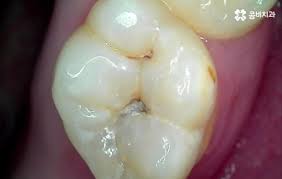

신경치료 후 치아는 내부 구조가 약해져 쉽게 깨질 수 있습니다. 크라운은 이를 보호하고, 씹는 기능과 심미성을 복원해주는 중요한 치료 단계로, 선택이 아닌 필수입니다.

1. 치과 신경치료란?신경치료(근관치료)는 치아 내부의 손상된 신경(치수)을 제거하고, 그 공간을 소독한 후 밀봉하여 감염을 막는 치료입니다. 충치가 깊어져 신경까지 침범하거나 외상, 감염